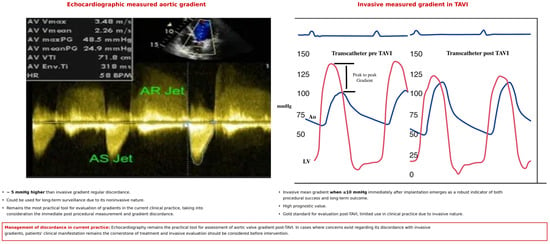

Echocardiography

Echocardiography